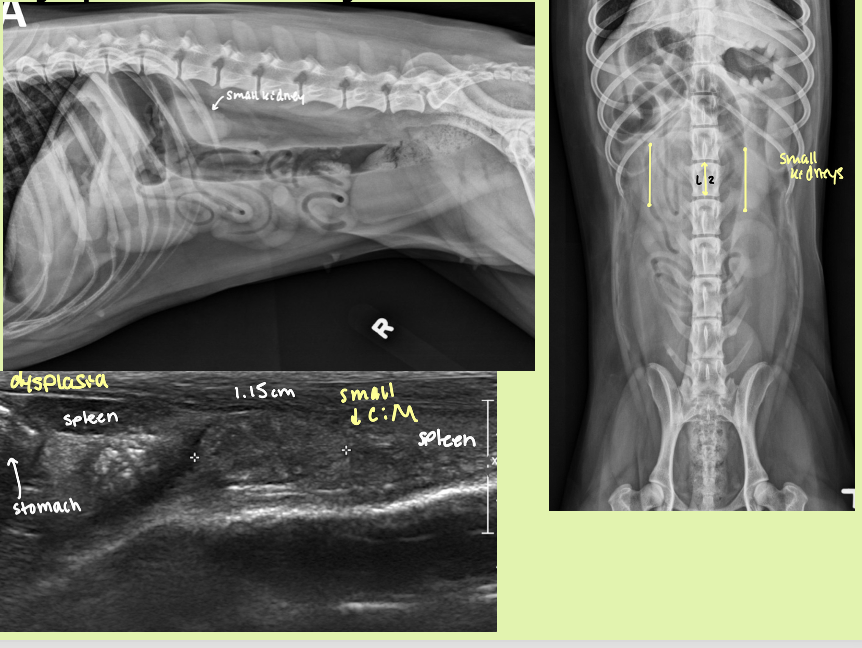

dog - 2.5-3.5 x length L2

cat - 1.9-3.2 x length L2

5 reasons for decreased kidney size

familial dysplasia, congenital disease

renal hypoplasia

YOUNG animal with renal disease that results in 2 small kidneys

hypoplastic/dysplastic kidneys